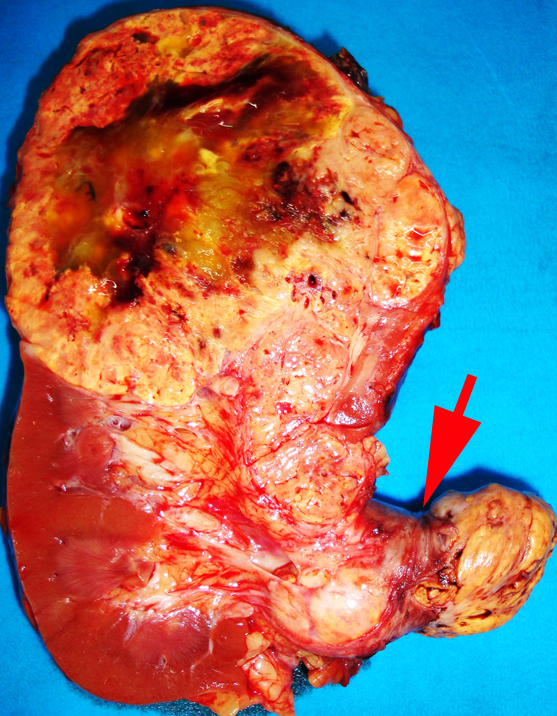

Adrenal gland involvement

In the current UICC/AJCC TNM staging classification (11), direct invasion of the adrenal gland is considered to be pT4 disease. This is a significant change from the 2002 UICC/AJCC TNM classification, in which adrenal gland invasion was considered to be pT3 disease. This change is based on reports that adrenal gland involvement has a significantly worse prognosis than that of perinephric fat invasion (36, 37). In view of this the adrenal gland should be carefully examined to assess whether it is involved by carcinoma, and if so, whether this is by direct invasion (pT4) or metastatic spread needs to be assessed (Fig. 4).

Figure 4

Figure 4. When the adrenal gland is involved it must be established whether it is direct invasion (pT4) or metastatic spread (pM1). In this example, both appear to be present.